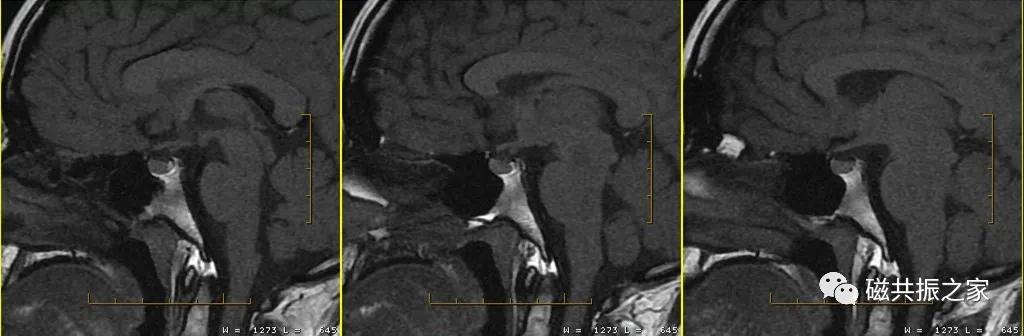

垂体大体解剖—— 垂体位于蝶鞍的小袋状颅骨凹陷处,直径约10mm,垂体通过垂体柄(漏斗=漏斗干+结节部)与下丘脑相连。垂体分为垂体前叶和垂体后叶;或腺垂体和神经垂体,见图△。

垂体的血供——垂体的双重血供系统与肝脏的血供系统类似,正常情况下,垂体前叶由脑底动脉环分出的垂体上下动脉所形成的门脉系统间接供血,垂体后叶由颈内动脉行经海绵窦后部时发出的垂体下动脉供血,垂体柄则接受来自垂体上动脉和垂体下动脉的血液。垂体前叶和后叶有相同的静脉引流,均有直接的引流静脉,经垂体下静脉引流至硬脑膜静脉窦,见图△。

矢状位是显示垂体前后叶最理想的方位。

在不同的年龄阶段,垂体的MRI 信号有所不同,新生儿整个垂体在T1WI 上表现为高信号,约6周以后,垂体前叶的信号强度逐渐减弱并最终与脑皮质相似,而垂体后叶组织内具有较多的神经分泌囊泡则表现为高信号,若高信号缺失则可能与中枢性尿崩症或垂体腺瘤受压有关。

腺垂体可以分泌多种激素,其在T1WI上呈相对低信号,与脑皮质信号相仿;神经垂体虽然不分泌激素,但其可储存下丘脑分泌的激素,在T1WI上常表现为高信号。

最理想的冠状位图像:同一层面视交叉、垂体柄和垂体均能清晰显示,共同组成“工”字结构。